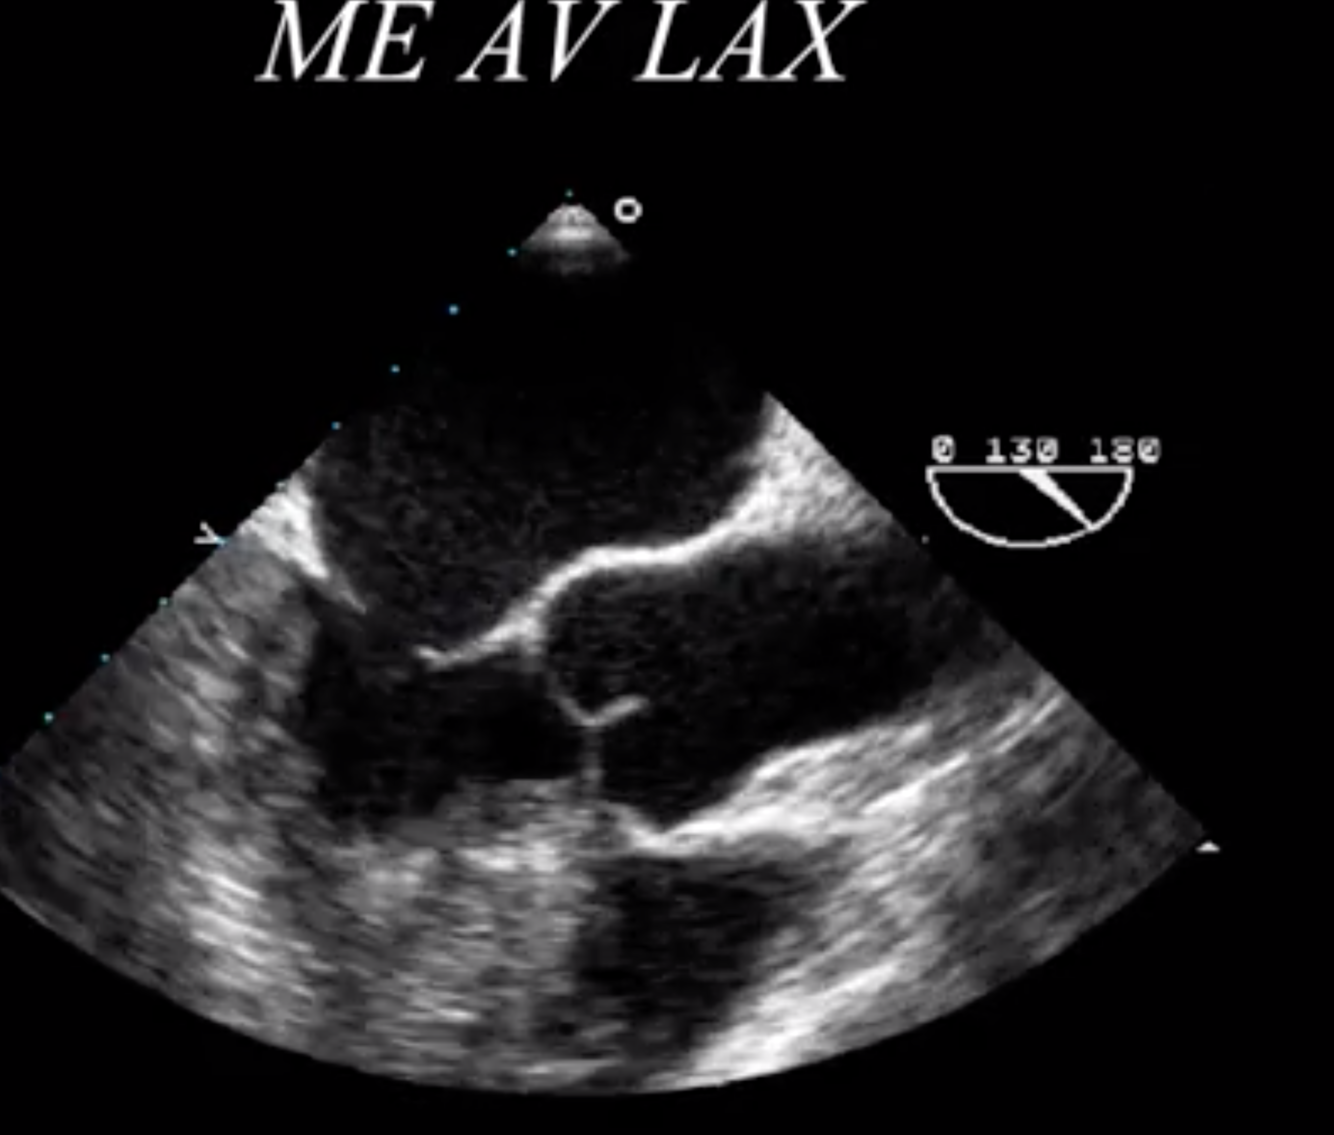

What is the measurement seen here?

Sinus of Valsalva

What is the blue arrow indicating?

Sinotubular Ridge or Sinuotubular Junction

What is seen in red?

Aortic Annulus

What TEE view is utilized to assess AI Jet / LVOT diameter to assess quantitatively for AI?

Mid Esophageal Aortic Valve Long Axis